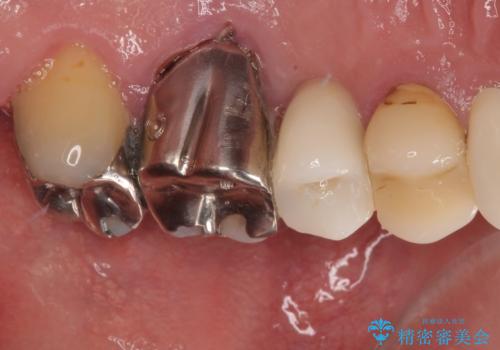

- 今回ご紹介するのは、左上の小臼歯(第二小臼歯)の治療を希望されて来院された患者様です。

診査の結果、該当歯は**虫歯が歯肉の奥深くまで進行し、根だけが残っている状態**でした。

このようなケースでは、歯を残すことが難しく、従来なら抜歯後に一定の治癒期間をおいてからインプラント治療を行うのが一般的です。